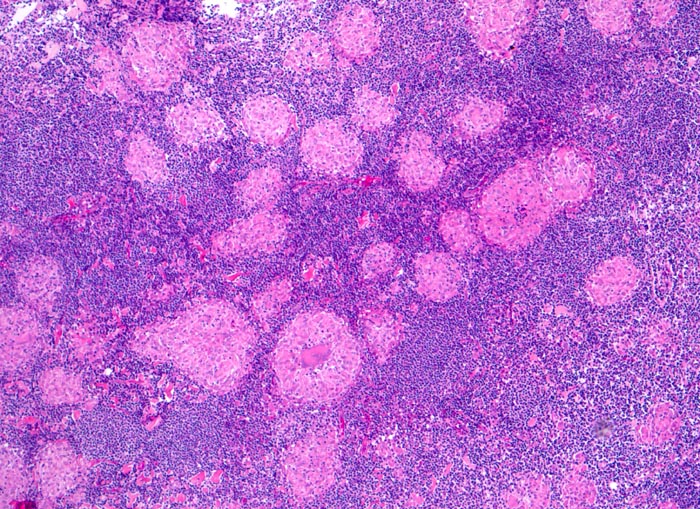

Sarkoidosegranulome bestehen aus Epitheloidzellen mit einem peripheren Lymphozytensaum. Mehrkernige Riesenzellen, meistens solche vom Langhans-Typ mit hufeisenförmig angeordneten Kernen und Asteroidkörperchen (> 4173) können zusätzlich vorhanden sein. Diese Granulome enthalten meist keine Nekroseherde (=produktives Granulom). Man findet diesen Granulomtyp hauptsächlich in Lymphknoten, aber auch in inneren Organen und in der Haut. Die Sarkoidosegranulome zeigen in späteren Stadien eine charakteristische perigranulomatöse und die Granulome septierend unterteilende Fibrose (> 4015).

• Wenig erhaltenes Lymphknotengewebe (blau).

• Konfluierende Granulome aus grossleibigen Epitheloidzellen.

• Wenige mehrkernige Riesenzellen.

• Kleinere Nekroseareale im Zentrum grösserer Granulome. (Die Nekrosen sind untypisch für die Sarkoidose, können aber bei grossen Granulomen gelegentlich vorkommen).

• Perigranulomatöse Fibrose. Das sollte der Kliniker dem Pathologen mitteilen: